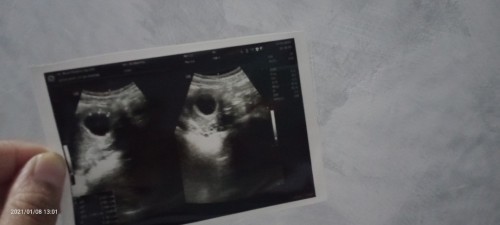

9 Minggu di USG hasilnya BO. Apa ada yg seperti saya bunda?

Rasanya ngga karuan Bun, baru hamil anak pertama.